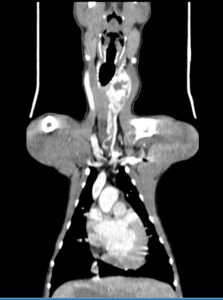

“The next step was to explore if the growth was operable so our specialist diagnostic imaging service performed an advanced CT scan to establish whether surgery could be performed.

“LVS is one of only a handful of specialist centres to have this advanced imaging option in central London and it was very important in this case.

“The CT images pinpointed the large growth within the left thyroid gland in Lenny’s neck and we were confident we could operate successfully and significantly increase the length and quality of his life.”